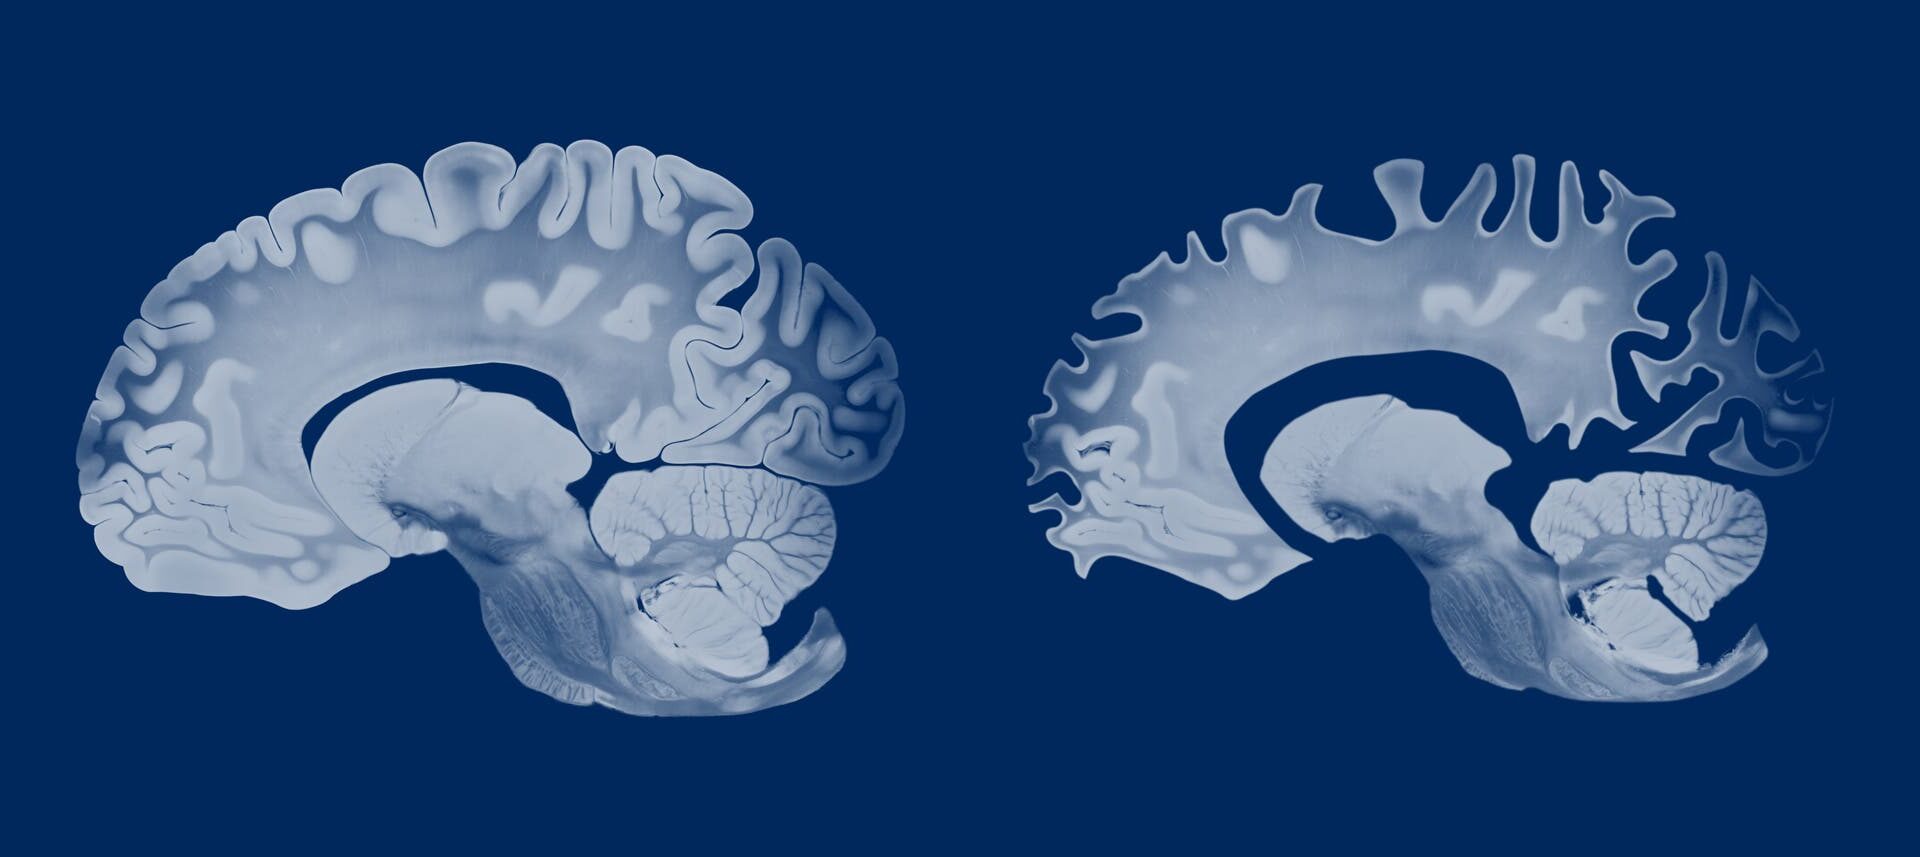

Ab Mitte 30 beginnt das Gehirn zu schrumpfen. Mit neurodegenerativen Erkrankungen wie Alzheimer hängt dieser normale Alterungsprozess aber offenbar nicht zusammen. Dabei nimmt das Hirnvolumen deutlich drastischer ab (im Bild rechts).

Die Alzheimerkrankheit geht ebenfalls mit einer Hirnschrumpfung einher, wenn auch in deutlich drastischerem Ausmaß. Man könnte daher annehmen, dem normalen altersbedingten Rückgang des Hirnvolumens und der Atrophie durch Alzheimer würden vergleichbare Ursachen zu Grunde liegen. Da Frauen statistisch gesehen deutlich häufiger von der neurodegenerativen Erkrankung betroffen sind, müsste in dem Fall das weibliche Gehirn stärker vom Volumenrückgang betroffen sein als das männliche – insbesondere jene Hirnregionen, die durch Alzheimer am schnellsten geschädigt werden, wie der Hippocampus. Die Studie ergab aber das Gegenteil, weshalb die Fachleute davon ausgehen, dass die strukturellen Veränderungen im Alter auf andere Prozesse zurückgehen als jene bei Demenz.